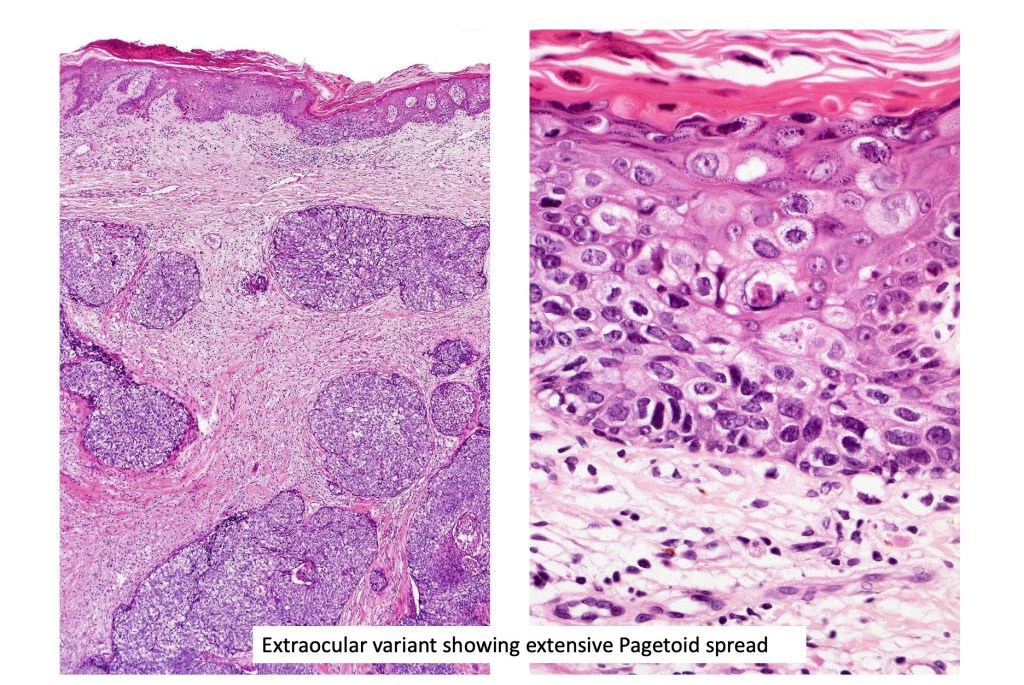

•May be associated with Pagetoid spread

•Periocular shave biopsies can be misleading and easily mistaken for Bowen’s disease